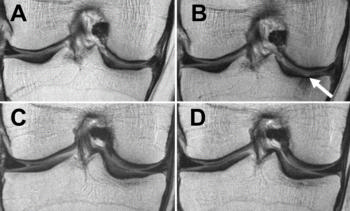

Figure 4. MRIs of the right knee obtained with sagittal intermediate-weighted fast spin-echo fat-suppression sequence at, A, C, baseline and, B, C, after 48 months. Patients were an obese 57-year-old woman with stable weight and mild knee pain (Western Ontario and McMaster Universities Arthritis Index (WOMAC) pain subscale score of 5 at baseline; baseline BMI, 31.4 kg/m2) (A, B) and an obese 59-year-old woman with weight loss (approximately 8.5 percent decrease in BMI) over 48 months and mild knee pain (WOMAC pain subscale score of 6 at baseline; baseline BMI, 32.1 kg/ m2) (C, D). The woman with stable weight developed a maceration of the medial meniscus (arrow) (medial meniscus Whole-Organ Magnetic Resonance Imaging Score (WORMS) of grade 0 in A and grade 4 in B) and thinning of the cartilage of the medial femoral condyle. In contrast, no meniscal defects (arrows) were seen on C or D (medial meniscus WORMS grade 0) in the participant with weight loss.